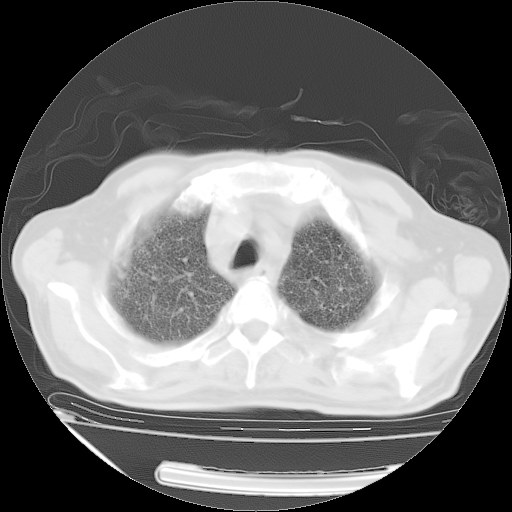

经过24天治疗,岳父的病情基本稳定。生活基本可以自理,可以下床活动。呼吸困难早已消失。体温基本正常。

只是甲强龙用80mg时血小板升到正常,改为60mg后又降到63×10*9/L。

主要治疗甲强龙80mg×14天,60mg×10天;同时抗结核(异烟肼+利福平+乙胺丁醇)。环磷酰胺0.1 tid 10天。

特别感谢胡教授、高管、桃子版主给出关键的治疗建议。桃版把所有肺部影像和全部临床资料请所在医院呼吸科、感染病科、结核科、临床免疫科专家会诊。临床免疫科专家制定了完整的治疗方案。